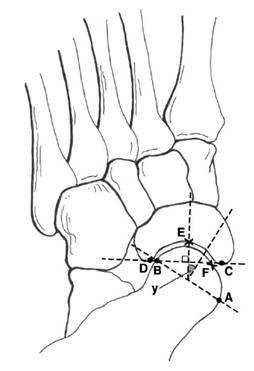

距舟覆盖角

1.         距骨关节面最内侧A,最外侧B,取两者连线

2.         舟骨关节面最内侧C,最外侧D,取两者连线

3.         两条直线垂线的夹角即为距舟覆盖角

正常人平均:10°(14°

扁平足平均:≥22

距骨第2跖骨角

1.         距骨颈取两条平行线,其中点的连线A

2.         2跖骨轴线B

正常足:<16°3-6°